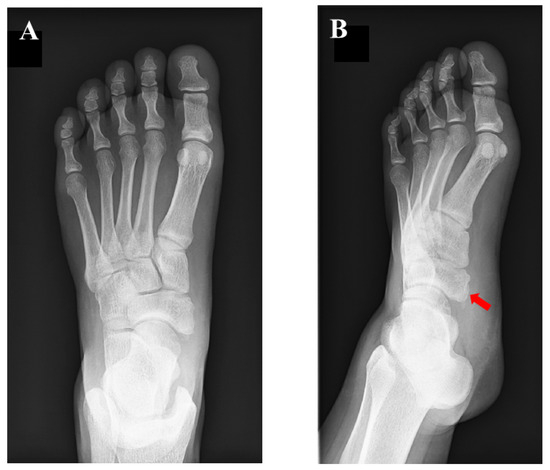

2. Case Presentation